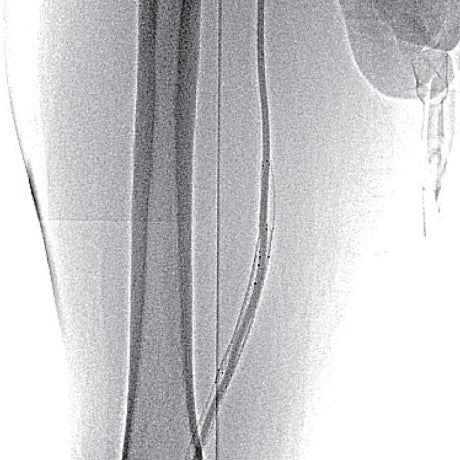

- SFA起始部にわずかなstumpを認め、膝窩動脈のP1-segmentまで連続する閉塞病変あり(図1)